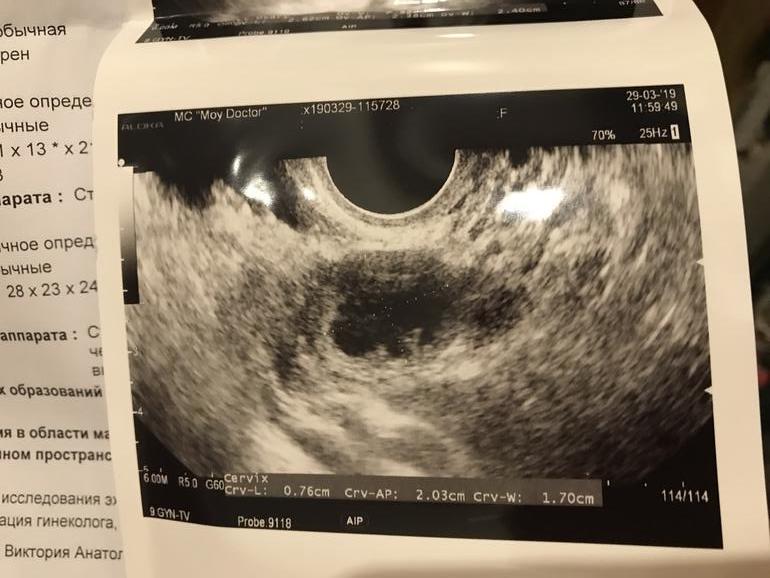

В итоге то ли узист неопытный , только не смогла определить, что это. То ли я не хочу верить в пролёт . Посмотрите , пожалуйста , что скажете ?

Была ли О и это формируется ЖТ? Хотя уже должно было сформироваться, если лопнул фолик 26 марта утром . Немного жидкости в позадиматочном есть . А в первую фазу, на 12 ДЦ не было никакой жидкости . Сегодня получается 17 ДЦ. И образование - киста или ЖТ 20 мм .

Эндометрий она сказала шикарный - 12 мм.

И еще сказала, что в этом образовании есть жидкость.